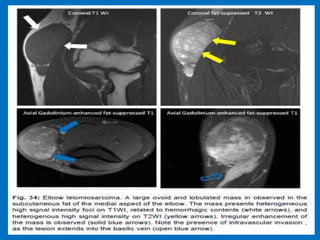

Soft tissue masses about the elbow joint.

Median nerve schwanoma.

Nerve-sheath tumor look-a-like, which turned out

to be a synovial sarcoma.

The final diagnosis at biopsy was Lymphoma.